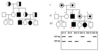

Autosomal Recessive Inheritance Pattern

- affected child born to UNAFFECTED parents

- parents usually carriers but ASYMPTOMATIC

- incr rate in consaguinous parents

- can affect either sex

recurrance risk of an auto-recessive diseases for each sibling of proband is…

25%